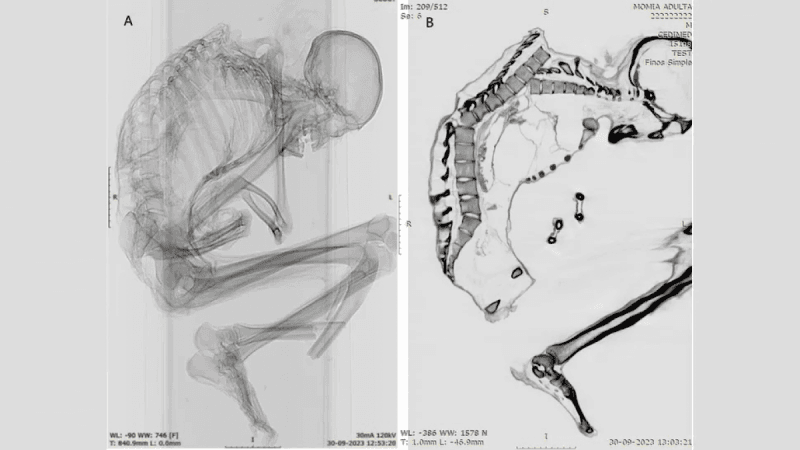

Каталіна Моралес і Франсіско Гаррідо, археологи з Національного музею природної історії в Сантьяго, використовували комп'ютерну томографію і рентгенівські знімки, щоб виявити найдрібніші деталі великої травми, яка, ймовірно, призвела до смерті чоловіка. Вони повідомили:

Травми, отримані чоловіком

За словами вчених, на верхній частині хребта чоловіка були виявлені численні незагоєні переломи. У нього також були переломи ребер, лопатки і ключиці, що вказує на "сильний удар по великій області" верхньої частини спини, показуючи, що "верхня ліва частина грудної клітки прийняла на себе основний удар". Удар змістив кілька хребців і зруйнував грудну клітку.

Крім того, дослідники виявили перелом біля основи хребта, який був результатом первинної травми верхньої частини спини. Вони написали:

"Травми верхньої і нижньої частин хребта зазвичай пов'язані з серйозним пошкодженням спинного мозку і високою смертністю".

Важливо, що на черепі, шиї та руках чоловіка не було виявлено жодних пошкоджень, що вказує на те, що удар стався, коли чоловік перебував у положенні головою вниз. Можливо, він активно займався видобутком корисних копалин або намагався захистити голову руками, коли на нього впав важкий предмет зверху. Подібні травми спостерігаються у людей, які постраждали від землетрусів, а також при виробничих травмах у лісовій, будівельній та гірничодобувній промисловості.